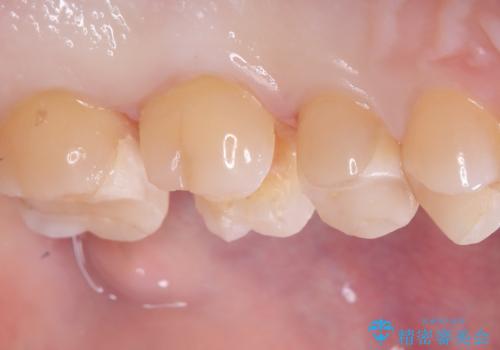

- 主訴:詰め物が欠けてしまった。

歯冠色インレーが一部欠けてしまい、他院にて部分的に樹脂のコーティング剤を付けてもらっている状態でした。

欠けている大きさが大きかったため、やり替えを提案しセラミックインレーでのやり替えとなりました。

他院にてセットしたセラミックインレーの一部が研磨では対応できない程大きく欠けてしまっていたため、やり替えとなりました。再度欠けぬよう、歯質を削り厚みを確保しています。